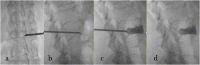

Vertebral fracture (VF) is a common condition with >160,000 patients affected every year in North America and most of them with affected lumbar vertebrae. The management of VF is well known and defined by many protocols related to associated clinical neurological symptoms, especially in case of the presence or absence of myelopathy or radicular deficit. In this article, we will explore the percutaneous stabilization of the lumbar spine by showing the newest approaches for this condition.